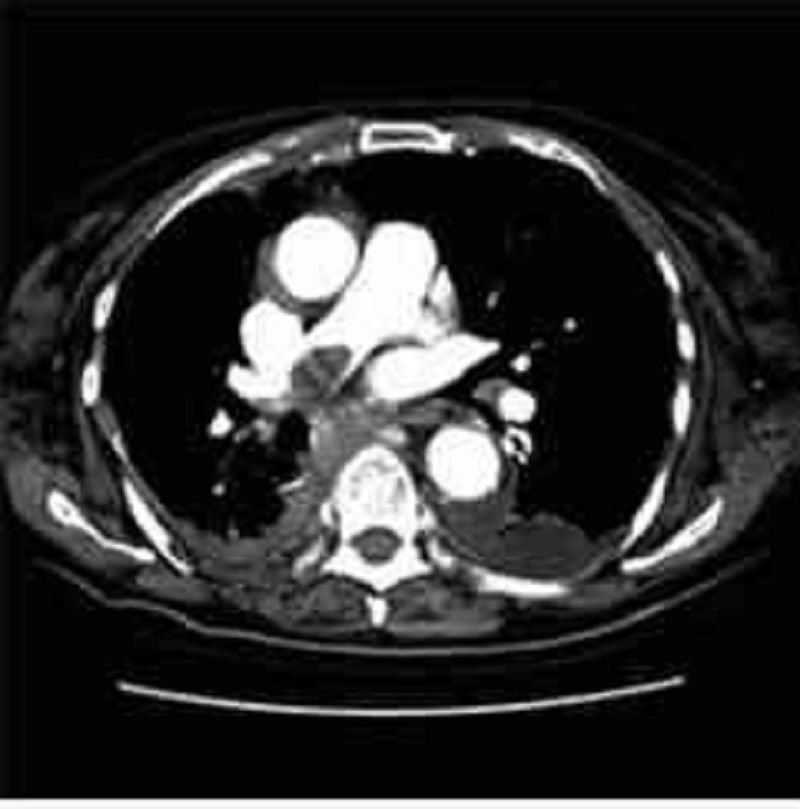

A 76-year-old woman presents with acute onset of persistent back pain and hypotension. A CT scan is obtained (shown below), and the patient is taken emergently to the operating room. Three days after surgery she complains of abdominal pain and bloody mucus per rectum. Which of the following is the most likely diagnosis?

Ischemia of the left colon